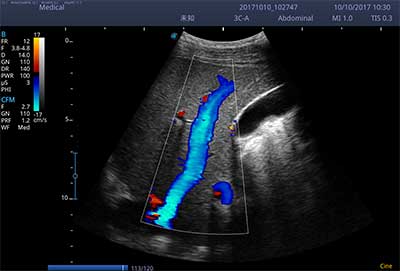

E3便携式彩色多普勒超声诊断系统拥有专业超声技术平台、高度集成化的硬件模块和结构设计、简便的操作流程、支持三探头接口全激活,兼顾了优质图像、轻便机身以及台便两用的临床使用需求。无论在常规超声科门诊检查,还是在急诊、麻醉、ICU、户外等各种应用场景。都能给您带来流程的操作体验。